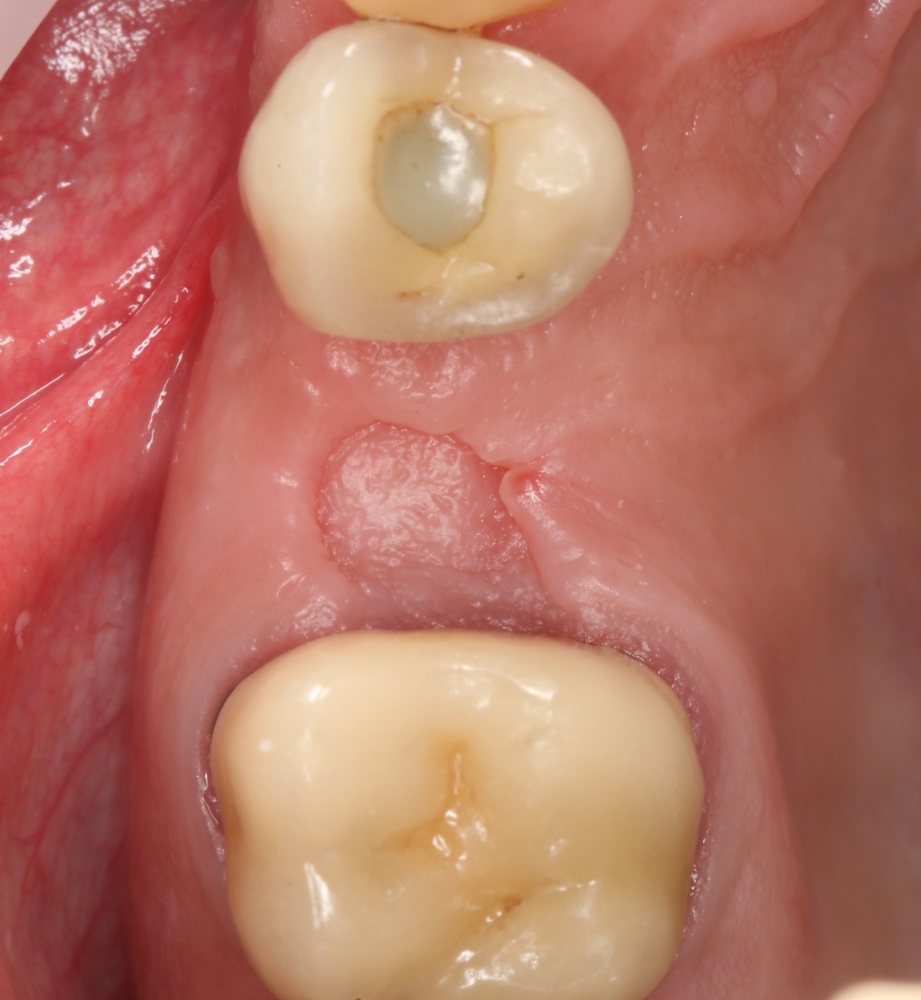

Мы встретились как старые друзья. Честно признаюсь, я очень переживал. Я ожидал увидеть какую-нибудь жуть, утраченную кость, периимплантит, разрушенный вхлам протез и всё такое. Но… всё оказалось не так плохо:

Но фиг с ними, с протезами. Это временные композитные коронки, их не так уж сложно заменить. Меня волнует другой вопрос:

Для этого мы сделали КЛКТ:

И КЛКТ показала нам, что с имплантатами и окружающей костью всё зашибись. Через 12 лет после операции, отсутствия наблюдения, пофигизма в замене временных коронок! Нужны ли тебе еще какие-нибудь доводы в пользу долгосрочной эффективности метода?